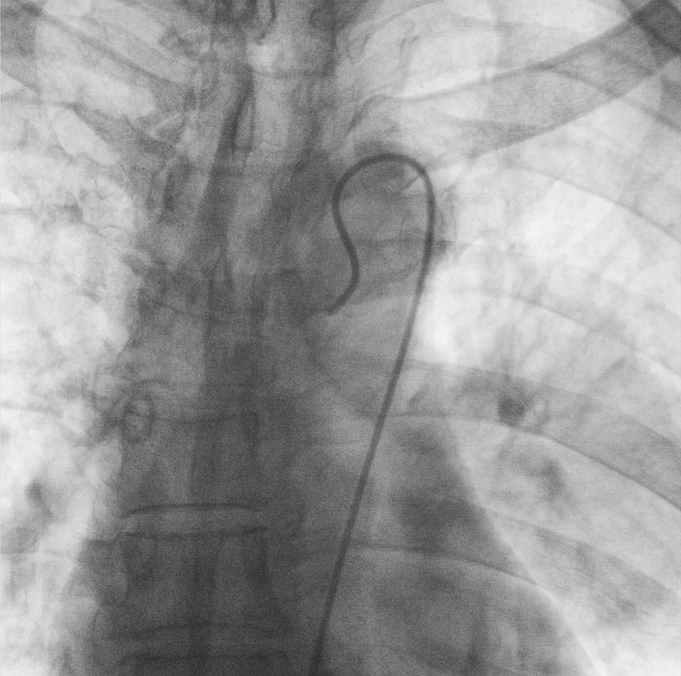

支气管动脉栓塞+化疗灌注术

在普爱医疗移动式平板介入中C影像的引导下,医生为患者实施双侧支气管动脉栓塞+化疗灌注术。

在微导丝的配合下,先后分别超选择①至3支左侧支气管动脉肿瘤供血动脉,经微导管推注栓塞微粒球栓塞肿瘤动脉。栓塞结束后,再次用移动式平板介入中C做造影检查,见肿瘤染色消失。